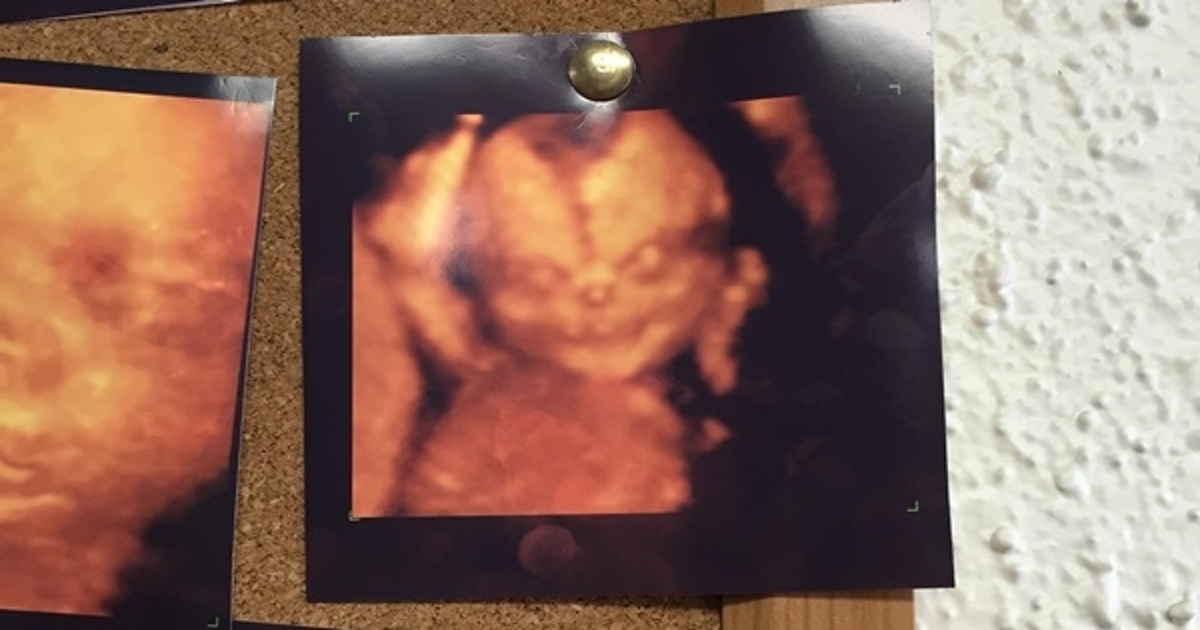

เผยภาพอัลตราซาวด์ 4D ของเด็กแบบน่าสยอง มองกล้องแสยะยิ้ม เหมือนกับหนังผี ทำเอาสามีภรรยา กลับไปอัลตราซาวด์แบบเดิมดีกว่า

เมื่อวันที่ 16 สิงหาคม 2558 เว็บไซต์ mirror.co.uk รายงานว่า พ่อแม่คู่หนึ่ง ที่กำลังรอการมาของลูกน้อย สมาชิกคนใหม่ของครอบครัว ต้องเกิดอาการขนหัวลุก เมื่อพวกเขาได้รับเห็นภาพอัลตราซาวด์แบบ 4D ของเด็กน้อยกำลังแสยะยิ้มให้กล้อง ประหนึ่งหลุดออกมาจากหนังผีก็มิปาน

ทั้งนี้ ผู้ใช้เว็บไซต์ Reddit นามว่า itsallrelative ได้โพสต์ภาพดังกล่าวลงในโลกออนไลน์ หลังจากที่เขาและภรรยากำลังจะไปทำอัลตราซาวด์ที่คลินิกแห่งหนึ่ง และเห็นภาพอัลตราซาวด์แบบ 4D ที่ติดอยู่กับกระดานในคลินิก ซึ่งภาพนั้นดูจะแตกต่างจากภาพอื่น ๆ โดยเป็นภาพที่คล้ายกับเด็กแสยะยิ้มอย่างท้าทาย และส่งแววตาชั่วร้ายออกมา

"ผมและภรรยากำลังจะไปตรวจครรภ์ด้วยอัลตราซาวด์แบบ 4D สำหรับลูกของเราที่กำลังจะเกิด พอเห็นภาพนี้ พวกเราเปลี่ยนใจทันที"

อย่างไรก็ตาม ยังมีคนบอกว่า ภาพนี้อาจจะถูกปรับเปลี่ยนจนบิดเบี้ยวเนื่องจากคุณภาพของภาพที่ไม่ดีก็เป็นได้

ภายหลังจากที่มีคนลงภาพนี้เพียง 24 ชั่วโมง ก็มีคนเข้ามาชมถึง 529,000 ครั้งและมีคนคอมเม้นท์นับร้อย และมีบางคนที่เข้ามาบอกว่า "นี่คือภาพจากกระดานในห้องรอ แน่นอนว่ามันตอกย้ำความมั่นใจของผมมากขึ้น ทำให้ผมและภรรยา กลับไปอัลตราซาวด์แบบธรรมดาเหมือนเดิม"